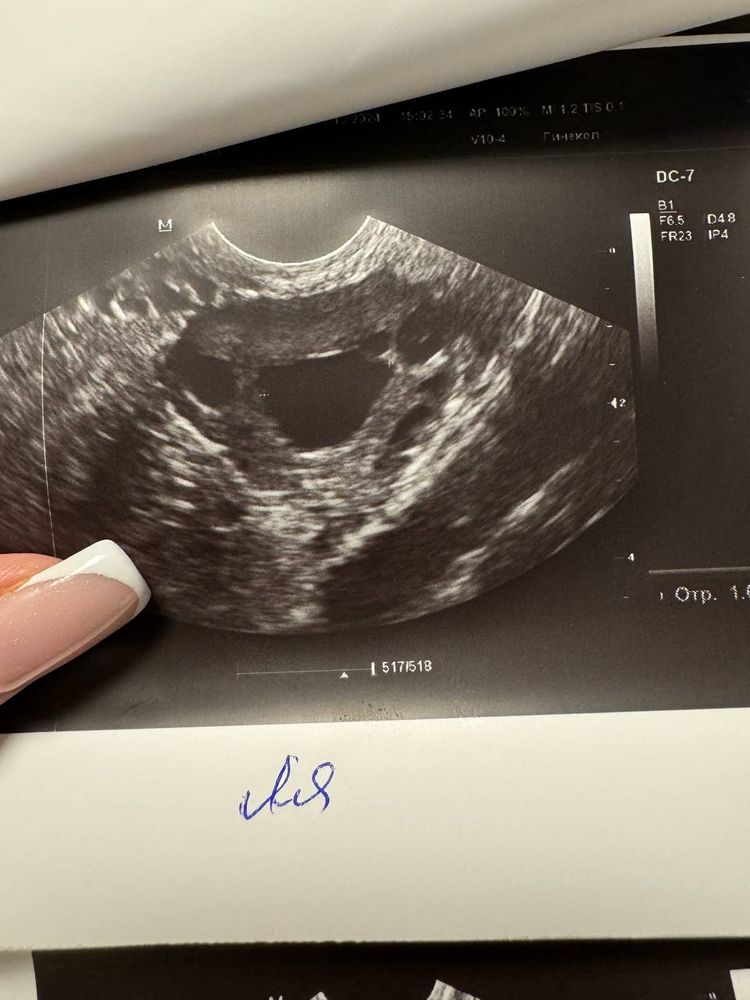

4.12.2024 я ходила на узи, там слева снова якобы «доминантный фолликул» 16,3 мм. При этом эндометрий 4,7.

При этом всем, он такой же странной формы - как был в октябре (овальный такой больше, не круглый). Так вот, у меня вопрос - что это, блин, такое? Это тот же самый фолликул? Киста? Но кисты вроде от 30 мм, а у меня был 23 и теперь 16…